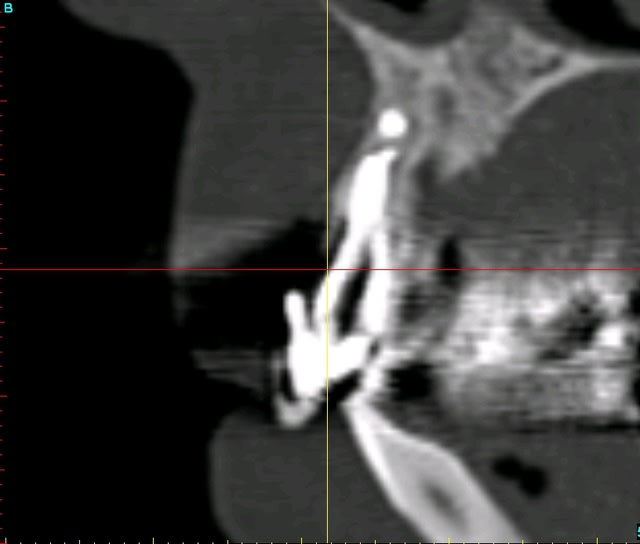

Purée, tu prends des risques énormes en fourrant ton bio oss puis en vissant les implants dans la masse de bio oss, de un, et sans membraner l'interface pilier implant, de deux...

Je suis peut-être vieux jeu mais c'est, à mon avis, dangereux d'un point de vue bactériologique.

c'est pas la première fois que je fais çà...;-)

et çà me donne plutôt de bons résultats

après tout...le périoste n'est-il pas la meilleure membrane?

par contre il faut veiller à avoir une bonne étanchéité au niveau des sutures...